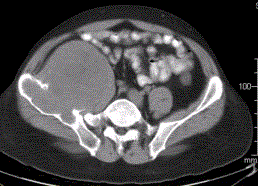

患者男,28岁,右下腹及臀部疼痛5个月余。查体:右髂骨外后侧压痛,右下腹可触及一软组织包块,质韧,固定。行骨盆正位CR、骨盆CT及MR扫描见下图。...

问题 患者男,28岁,右下腹及臀部疼痛5个月余。查体:右髂骨外后侧压痛,右下腹可触及一软组织包块,质韧,固定。行骨盆正位CR、骨盆CT及MR扫描见下图。 此病变最可能的诊断是

选项 A.骨囊肿 B.动脉瘤样骨囊肿 C.骨结核 D.骨巨细胞瘤 E.硬韧带样纤维瘤

答案 B